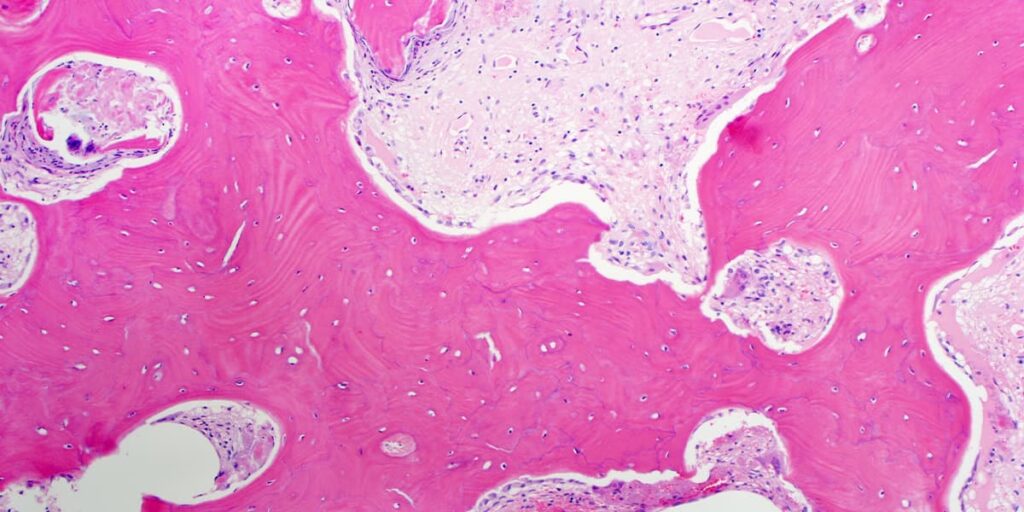

Hæmatoxylin og Eosin (H&E)

Dette er den mest anvendte farvningsmetode i histologi. Det er en kombination af to farvestoffer:

- Hæmatoxylin: Et basisk farvestof, der farver sure strukturer, såsom cellekernen (der indeholder DNA), i en blå/lilla nuance.

- Eosin: Et surt farvestof, der farver basiske strukturer, såsom cytoplasma og ekstracellulære proteiner, i forskellige nuancer af pink og rød.

Sammen giver H&E-farvning et fremragende overblik over den generelle vævsarkitektur og er ofte tilstrækkelig til at stille en diagnose.